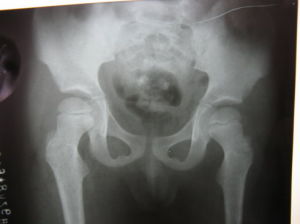

(四)X線檢查

X線片主要表現為髖關節骨性結構無異常,有時可見關節囊陰影膨隆。關節腔積液嚴重時可見股骨頭向外側移位,關節間隙增寬。